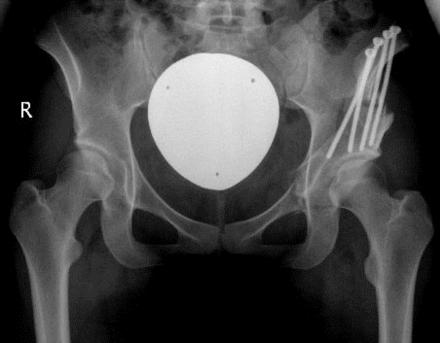

In residual hip dysplasia periacetabular osteotomy (PAO) can improve insufficient coverage of the femoral head. It requires a broad dissection of the pelvic bones and detachment of muscle insertions, however. We have developed a modification of the Bernese periacetabular osteotomy with reduced soft tissue exposure. It uses two small skin incisions and offers therefore the perspective of nicer scars but also increases the risk of technical complications due to impaired vision. To be able to draft these risks, the clinical and radiographic results of 23 patients with PAO through the modified Smith-Petersen approach of Ganz (group A) and 24 patients with our two-incision modification (group B) have been reviewed retrospectively with an average follow-up of 19 (group A) and 12 (group B) months postoperatively.Functional improvement (Harris Hip Score) and center-edge-angle normalization did not differ significantly in both groups. Scars of patients in group B were significantly shorter. However, the overall patient satisfaction (as measured with a visual analogous scale) was the same in both groups. 4 patients in group A and one patient in group B developed superficial or deep wound infections.In conclusion, the experience with our cohort study showed that approach-related morbidity can be reduced without increasing the risk for the individual patient. This observation clearly holds a promise for further minimal invasive approaches as well as for further morbidity reduction of PAO.

在残留性髋关节发育不良中,髋臼周围截骨术(PAO)可改善股骨头覆盖不足的情况。然而,该手术需要广泛剥离骨盆骨并切断肌肉附着点。我们对伯尔尼髋臼周围截骨术进行了改良,减少了软组织暴露。该改良术式采用两个小切口,因此有望形成更美观的瘢痕,但由于视野受限也增加了技术并发症的风险。为了评估这些风险,我们回顾性分析了23例采用改良甘茨史密斯-彼得森入路行PAO手术的患者(A组)和24例采用我们的双切口改良术式的患者(B组)的临床及影像学结果,术后平均随访时间分别为19个月(A组)和12个月(B组)。两组患者的功能改善情况(Harris髋关节评分)和中心边缘角正常化情况无显著差异。B组患者的瘢痕明显更短。然而,两组患者的总体满意度(采用视觉模拟量表测量)相同。A组有4例患者和B组有1例患者发生了浅表或深部伤口感染。总之,我们的队列研究经验表明,在不增加个体患者风险的情况下,可以降低手术相关的发病率。这一观察结果显然为进一步的微创方法以及降低PAO的发病率带来了希望。